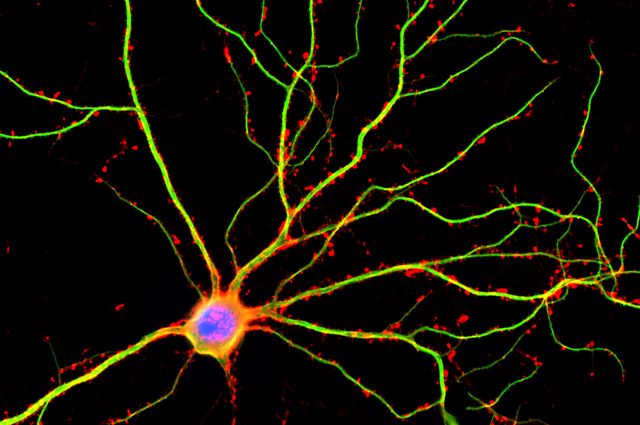

Based on Strong Scientific Foundations

What tDCS research shows:

-

Improves cognitive performance

-

Reduces symptoms of depression

-

Helps Alzheimer’s and dementia patients

-

Enhances learning and memory formation

-

Supports recovery after neurological injury

A leading study by Benussi et al. (2020) found:

“Significant increase of intracortical connectivity and improvement in behavioral symptoms in dementia patients after tDCS.”